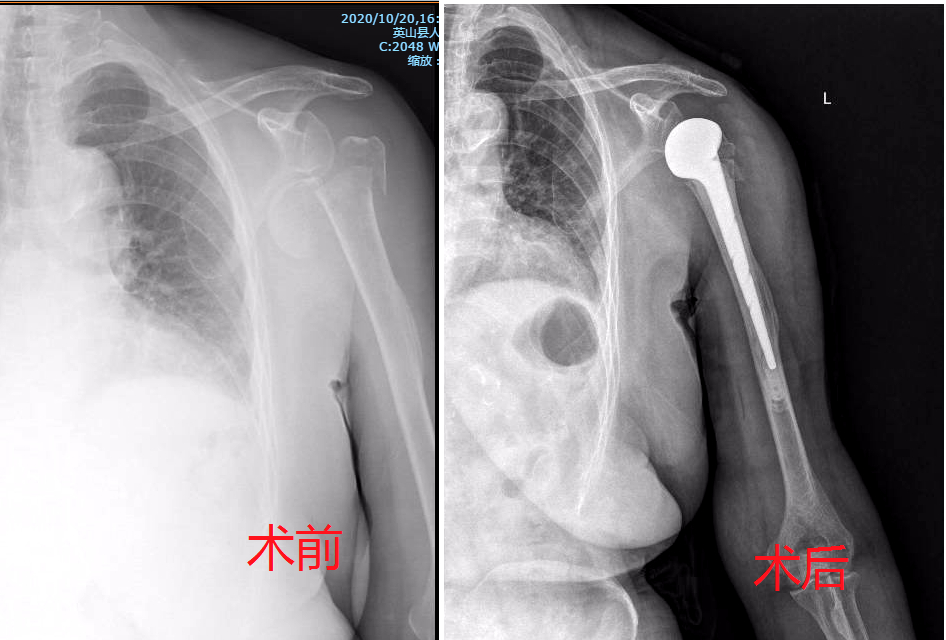

本网讯 (通讯员 邓健 编辑 方宝生) 10月23日,英山县人民医院成功开展首例人工肩关节置换术,填补了该院人工肩关节置换领域的空白。

为确保手术成功,医院组织专家团队,多学科进行会诊。通过查阅各种文献资料,主治医师邓健进行术前CT、磁共振、X-Ray……一步步完善手术准备。在充分准备的前提下,手术依次取出脱位的肱骨头、安装假体、重建韧带,仅用了2个小时。经过手术治疗,术后3天患者已经能做一些简单的肢体动作,恢复良好。